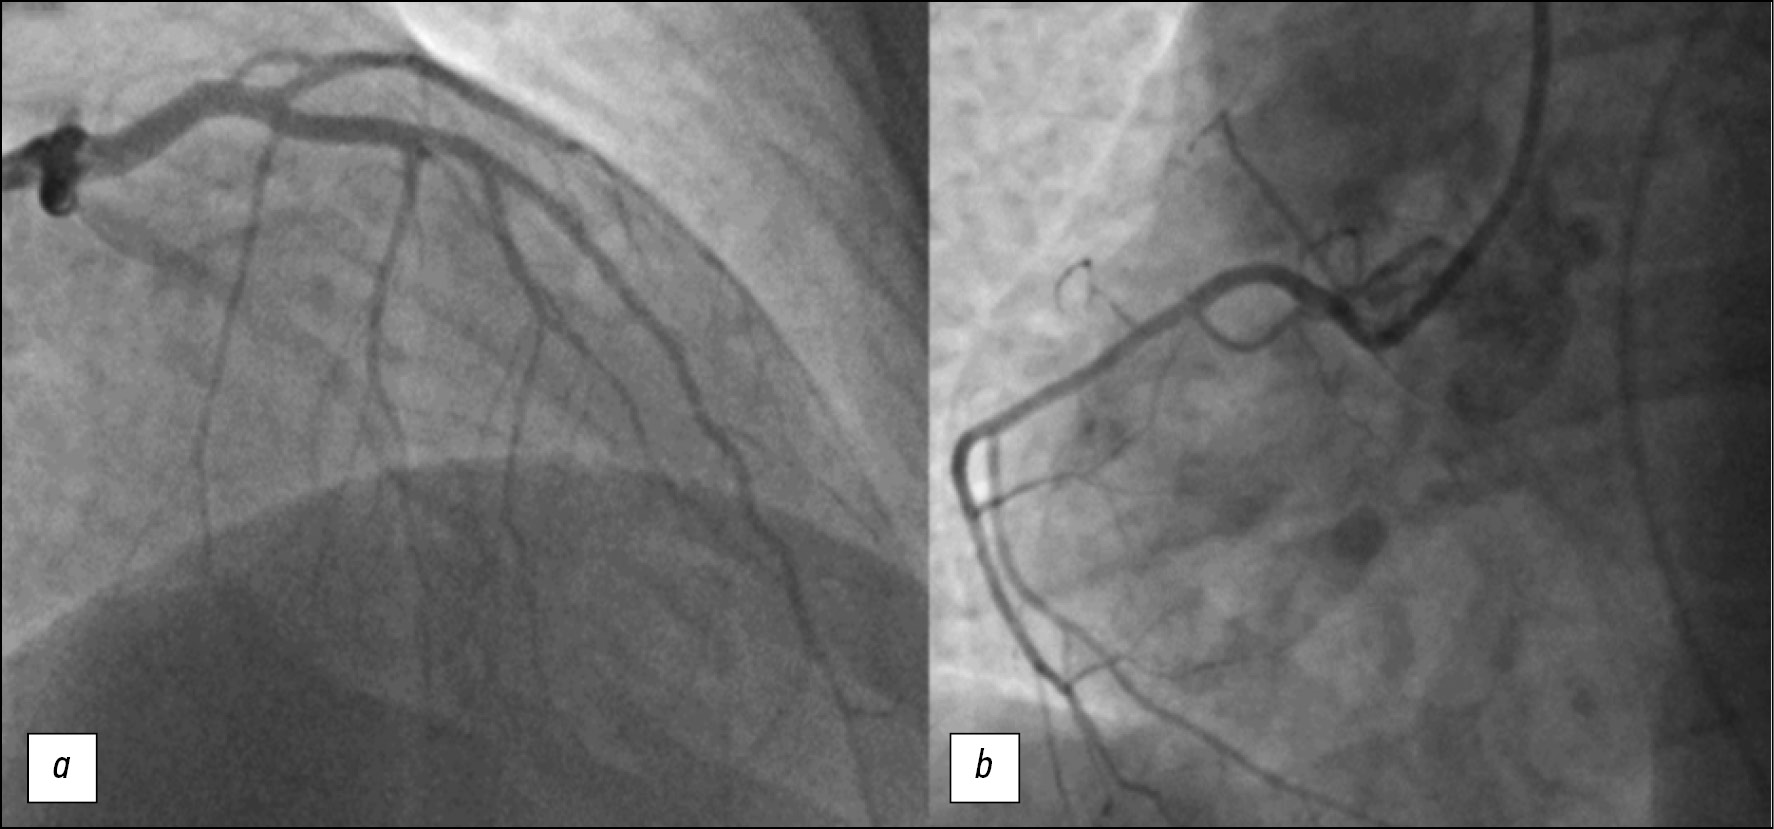

Based on the clinical picture, ECG changes, and elevated cardiac enzymes on admission, the diagnosis was ST-elevation myocardial infarction. Emergency coronary angiography (CAG) was performed, which showed no stenotic lesions of the coronary bed in the left (Figure 2, a) and right (Fig. 2, b) coronary arteries. Signs of moderate peripheral vasospasm were observed (Figure 2).

Fig. 2. Coronary angiography of patient M.: a — left coronary artery; b — right coronary artery.